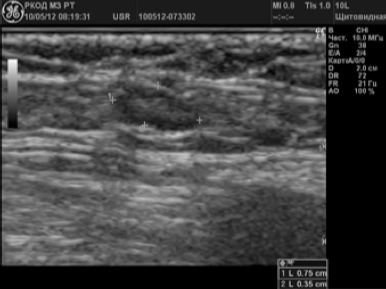

Рисунок 1.

Неизмененный паховый лимфатический узел

Ультразвуковыми критериями нормального (неизмененного) состояния лимфоузлов (рис. 1) считались 5:

- форма преимущественно овальная, вытянутая;

- границы — четкие, контуры — ровные;

- соотношение П/ПЗ>2,0;

- размер по длинной оси — не более 1,5 см;

- наличие дифференциации на кору и ворота (в норме по периферии ЛУ располагается гипоэхогенная часть — кора, а в центральной части — гиперэхогенная часть — ворота).

Нормальный лимфатический узел имеет овальную форму с преобладанием длины над шириной, чёткие, ровные контуры с дифференцированными структурными элементами (рис.1).